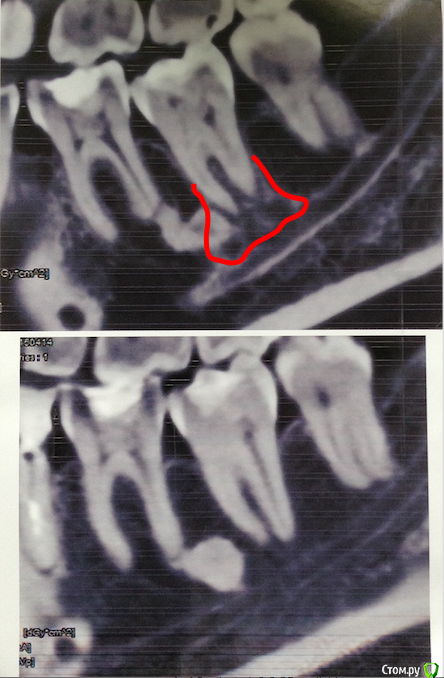

TFlow Опубликовано 15 сентября, 2018 Поделиться Опубликовано 15 сентября, 2018 (изменено) Здравствуйте!В 2015 году я поставила брекеты, предварительно сделав КТ, слепки и имея при этом старые ортопантомограммы (2 шт.) На старых снимках (от 2007 года) под нижними правыми шестёркой и семёркой было видно образование, которое мне всегда советовали не трогать, мол, их без показаний не удаляют. На КТ это образование тоже было видно. Ни рентгенолог, ни ортодонт противопоказаний на установку брекет-системы не указали.Через 4 месяца (зимой) после установки системы на нижнюю челюсть, внизу справа у меня появились непонятные боли в районе нижних коренных зубов. Было похоже на повышенную чувствительность и я использовала реминерализующий гель от РОКС. Казалось, помогает. Но потом он перестал помогать. Боли усиливались в холодную и ветреную погоду, на горячее-холодное-сладкое-солёное, а также при смене внешней температуры (например пришла с мороза в кафе или домой). Мысли у врача были, что это дёсна, гиперчувствительность зубов или "какие-то фантомные боли" (перед брекетами были удаления справа). Приступы потихоньку (это всё было очень растянуто по времени!) увеличивались по продолжительности (от 2 минут до 25-30 минут) и появлялись уже не только в мороз, но и летом.Через два года после начала периодических болей я сделала КТ всех зубов повторно (разница между двумя КТ три года, второй делала в июне 2018 года), после чего рентгенолог выдал мне диск с КТ и в бумажном виде панорамный снимок челюстей. Он опять успокоил меня насчёт образования под нижней семёркой справа, типа ничего особенного там не увидел (уверял, что посмотрел хорошо) и посоветовал пойти в неврологу и делать МРТ. Невролог поставил мне невропатию тройничного нерва и дисфункцию ВНЧС! (при нажатии заболел правый висок, а хруст я заметила давно, щелчков нет). МРТ головного мозга ничего не показала. Анализ крови на герпес - тоже. Невролог прописала витамины группы B и Габапентин курсом в 2 месяца. В итоге на Габапентине приступы всё равно были и особенно сильный, когда уже начало стрелять в правое ухо и появились неприятные ощущения в его районе вообще, был уже когда я закончила приём препарата (28 августа). Я опять полетела к неврологу (уже к другому, потому что к первому было невозможно записаться), он нащупал сильную спазмированность мышц в районе правого уха и виска, прописал Сирдалуд и иглоукалывание курсом из 8-ми сеансов (я его сейчас заканчиваю). После Сирдалуда, как мне кажется, у меня меньше онемение в правой нижней части лица. По назначению невролога сделала электронейромиографию (5 сентября), но конкретного участка повреждения тройничного нерва она не показала. Диагност сказала, это потому что ЭНМГ сделана не сразу после приступа, но так уж у меня получилось, а невролог сильно, как я поняла, на неё (ЭНМГ) рассчитывал.12 сентября опять случился приступ, когда ела сладкое на правой стороне. Болело примерно 30 минут и я заметила в этот раз, что болело уже как-то не внизу (где, как мне показывал рентгенолог, выходит нижняя ветка тройничного нерва), а в самих зубах, а именно нижние 6 и 7 справа. Я побежала к своему терапевту, она постучала по зубам и сделала реакцию на лёд, сильно заныла семёрка... 6 тоже реагировала, но 7 больше. В итоге врач отправила меня снова в клинику, где я делала обе КТ (до брекетов и после, с разницей в три года), и сказала, чтобы мне "покрутили" на компьютере это образование (оно же как раз под нижними правыми 6 и 7) и напечатали на бумаге именно участок с этим образованием (остеомой?). В итоге, в этой клинике мне открыли старую и новую КТ и... в общем, снимок прилагаю. Вверху на снимке - 2018 год, внизу - 2015 год. Общая КТ на фото - от июня 2018 года. Я в шоке. Что это? Там явное соединение "нечто" с тройничным нервом. Оно даже образование (остеому?) частично съело. Вот тройничный у меня и болел! И, возможно, ДВНЧС я заработала из-за этих болевых шоков! Дискомфорт в районе правого уха и виска, а также, как обнаружилось немногим позже ещё и небольшое сдвигание нижней челюсти влево - появились после приступа 28 августа. Я просто в ауте от "работы" рентгенолога в июне этого года. Как можно это просмотреть, когда уверял, что "всё посмотрел"? Теперь мне надо бежать к хирургу (буду искать опытных хирургов на следующей неделе), но решила пока написать сюда, чтобы морально начать к чему-нибудь готовиться и, наверное, просто выговориться.Кто-нибудь имеет представление, что это за размытая область на снимке под нижней семёркой? Оно прямо соединяется с тройничным нервом! И что может сделать хирург? Это ж, получается, какая-то дрянь меня, возможно, инфицирует уже больше 2-х лет и треплет нерв! Я действительно чувствую общую слабость (а через два месяца после появления болей у меня, кстати, впервые в жизни был сильный гайморит - правосторонний! вылечил врач-лор Аугментином и Назонексом), но температуры нет! (грипп в январе 2017 года, наверное, не в счёт - тогда многие болели, и в моей семье - тоже). Хотя во время приступов у меня ощущение, что меня как бы бросает "в пот", в эти моменты зубы у меня разомкнуты - наверное, инстинктивно боюсь сомкнуть. Впрочем, слабость, подавленность, наверное, может быть из-за стресса по поводу этих болей, новостей про ДВНЧС. А теперь вот это непонятное нечто...Помогите советом, пожалуйста! Изменено 15 сентября, 2018 пользователем TFlow Ссылка на комментарий

TFlow Опубликовано 15 сентября, 2018 Автор Поделиться Опубликовано 15 сентября, 2018 (изменено) Зачем лезть в эти дебри... Неврологи, МРТ, ЭНМГ... Мде. По сабжу: 1. Новообразование никакой роли не играет. 2. Ищите пульпит в зубах 46, 47, 48 и 18. Спасибо за ответ! Дык к неврологу побежала, потому что на КТ "всё ок" и "ищите причину болей тройничного нерва у невролога". Ну а невролог, поверя заключению рентгенолога (именитого у нас, кстати) и решив, что раз причина не в зубах, то делаем МРТ и пьём Габапентин... А вот эту "нарезку" КТ (где зона с образованием отдельно - за 2015 и за 2018 гг) я сделала буквально только вчера. А что это за образование, которое прямо на нерв ложится (прямо корни семёрки обволакивет )? На его месте в 2015 году чисто было... Изменено 15 сентября, 2018 пользователем TFlow Ссылка на комментарий

kramer Опубликовано 15 сентября, 2018 Поделиться Опубликовано 15 сентября, 2018 (изменено) И без КТ видно, что у вас на зубах 46 и 47 гигантские пломбы "впритык" с нервом (пульпой). А что это за образование, которое прямо на нерв ложится? Покажите стрелкой, что вы имеете ввиду Изменено 15 сентября, 2018 пользователем kramer 1 Ссылка на комментарий

TFlow Опубликовано 15 сентября, 2018 Автор Поделиться Опубликовано 15 сентября, 2018 И без КТ видно, что у вас на зубах 46 и 47 гигантские пломбы "впритык" с нервом (пульпой). Покажите стрелкой, что вы имеете ввиду По поводу пломб мне позавчера тоже так сказали - про впритык с пульпой. Но этим пломбам больше 10-ти лет, визуально всем врачам, кто смотрит, они нравятся. Пока рентген в руки не берут... Можно было, интересно, брекетами как-то их сдвинуть? (не знаю, как объяснить) А зону указала (как смогла) в стартовом своём посте. Ссылка на комментарий

kramer Опубликовано 15 сентября, 2018 Поделиться Опубликовано 15 сентября, 2018 Тем, что вы отметили красным, скорее всего являются питательные каналы с сосудами и нервами, которые идут от нижнечелюстного канала к зубу. Как водопровод. Такая же штука есть и 8 зуба на снимке, если присмотреться. Это норма, разумеется. Надо в клинике сделать пробы, которые выявят пульпитный зуб (если он есть). Фриз-тест, например. 2 Ссылка на комментарий

TFlow Опубликовано 15 сентября, 2018 Автор Поделиться Опубликовано 15 сентября, 2018 Тем, что вы отметили красным, скорее всего являются питательные каналы с сосудами и нервами, которые идут от нижнечелюстного канала к зубу. Как водопровод. Такая же штука есть и 8 зуба на снимке, если присмотреться. Это норма, разумеется. Надо в клинике сделать пробы, которые выявят пульпитный зуб (если он есть). Фриз-тест, например.А мне-то вчера в клинике, где "нарезку" делали, со страшными глазами сказали: "Там что-то образовывается!!" Они имели в виду в сравнении с 2015-м годом. Напугали меня до ужаса. Хотя почему раньше этих каналов не видно было? И именно седьмой зуб вчера и позавчера реагировал, кстати, на фриз-тест. Я правильно понимаю, это когда лёд прикладывают? Седьмой сразу ныл и потом не очень-то быстро отходил. Это лечить или удалять зуб? Я просто думаю, что этот "водопровод" дёргает тройничный нерв, больше нечему (судя по снимкам). Ссылка на комментарий